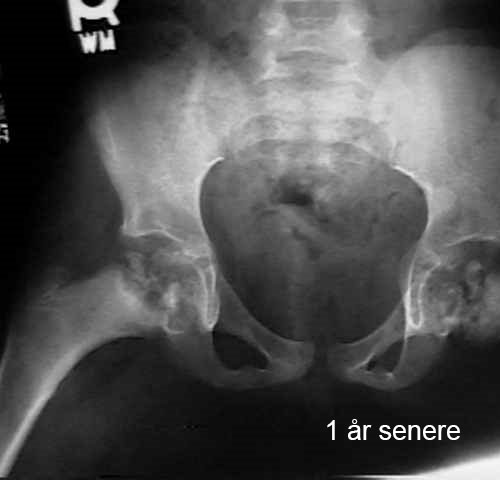

Lårbeinshodet dør delvis eller helt. Kroppen forsøker å løse dette ved å danne nytt beinvev og bryte ned det døde vevet. Det nye beinet er fortsatt svakt, noe som kan føre til at hoften mister sin runde form eller kollapser. Dette fører til deformasjon av hofteleddet. Bildene viser utviklingen av hoften hos et barn med Calvé-Legg-Perthes sykdom.